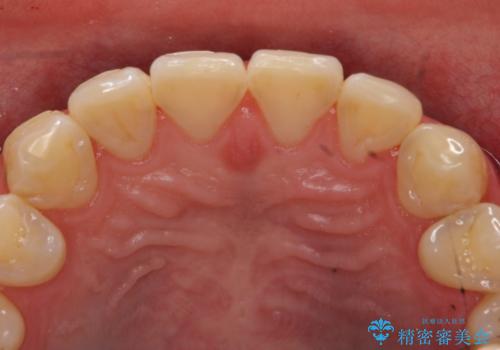

- 右上2、3番目の歯の色・形が気になるといらっしゃった方の症例です。

古い樹脂を除去後、オールセラミッククラウンによる補綴を行いました。

今回用いたオールセラミッククラウンは、ジルコニアフレームという白い素材の上にセラミックを盛っているため審美性が非常に高いのが特徴です。

またジルコニアは人工ダイヤモンドの材料にも使われているほど高い強度を持っており、そのためオールセラミッククラウンは審美性だけでなく、奥歯やブリッジの補綴も可能とするクラウンです。